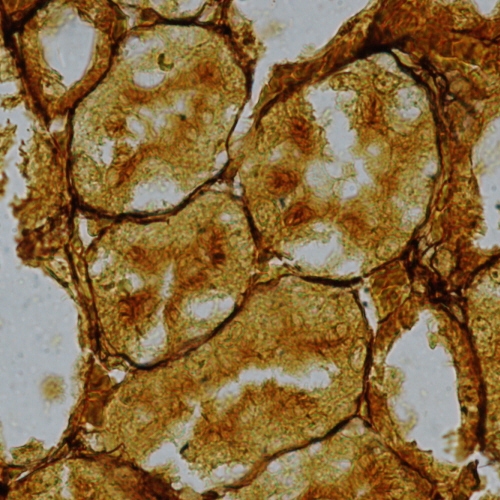

Reticular fibres (reticulin), thin fibrils of type III collagen, form a loose mesh in many support tissue and are particularly prominent just below the basement membrane. They form a network to support the cells in parenchymal organs like the liver and kidney.

Slide 48 Identify: Reticular fibers Liver